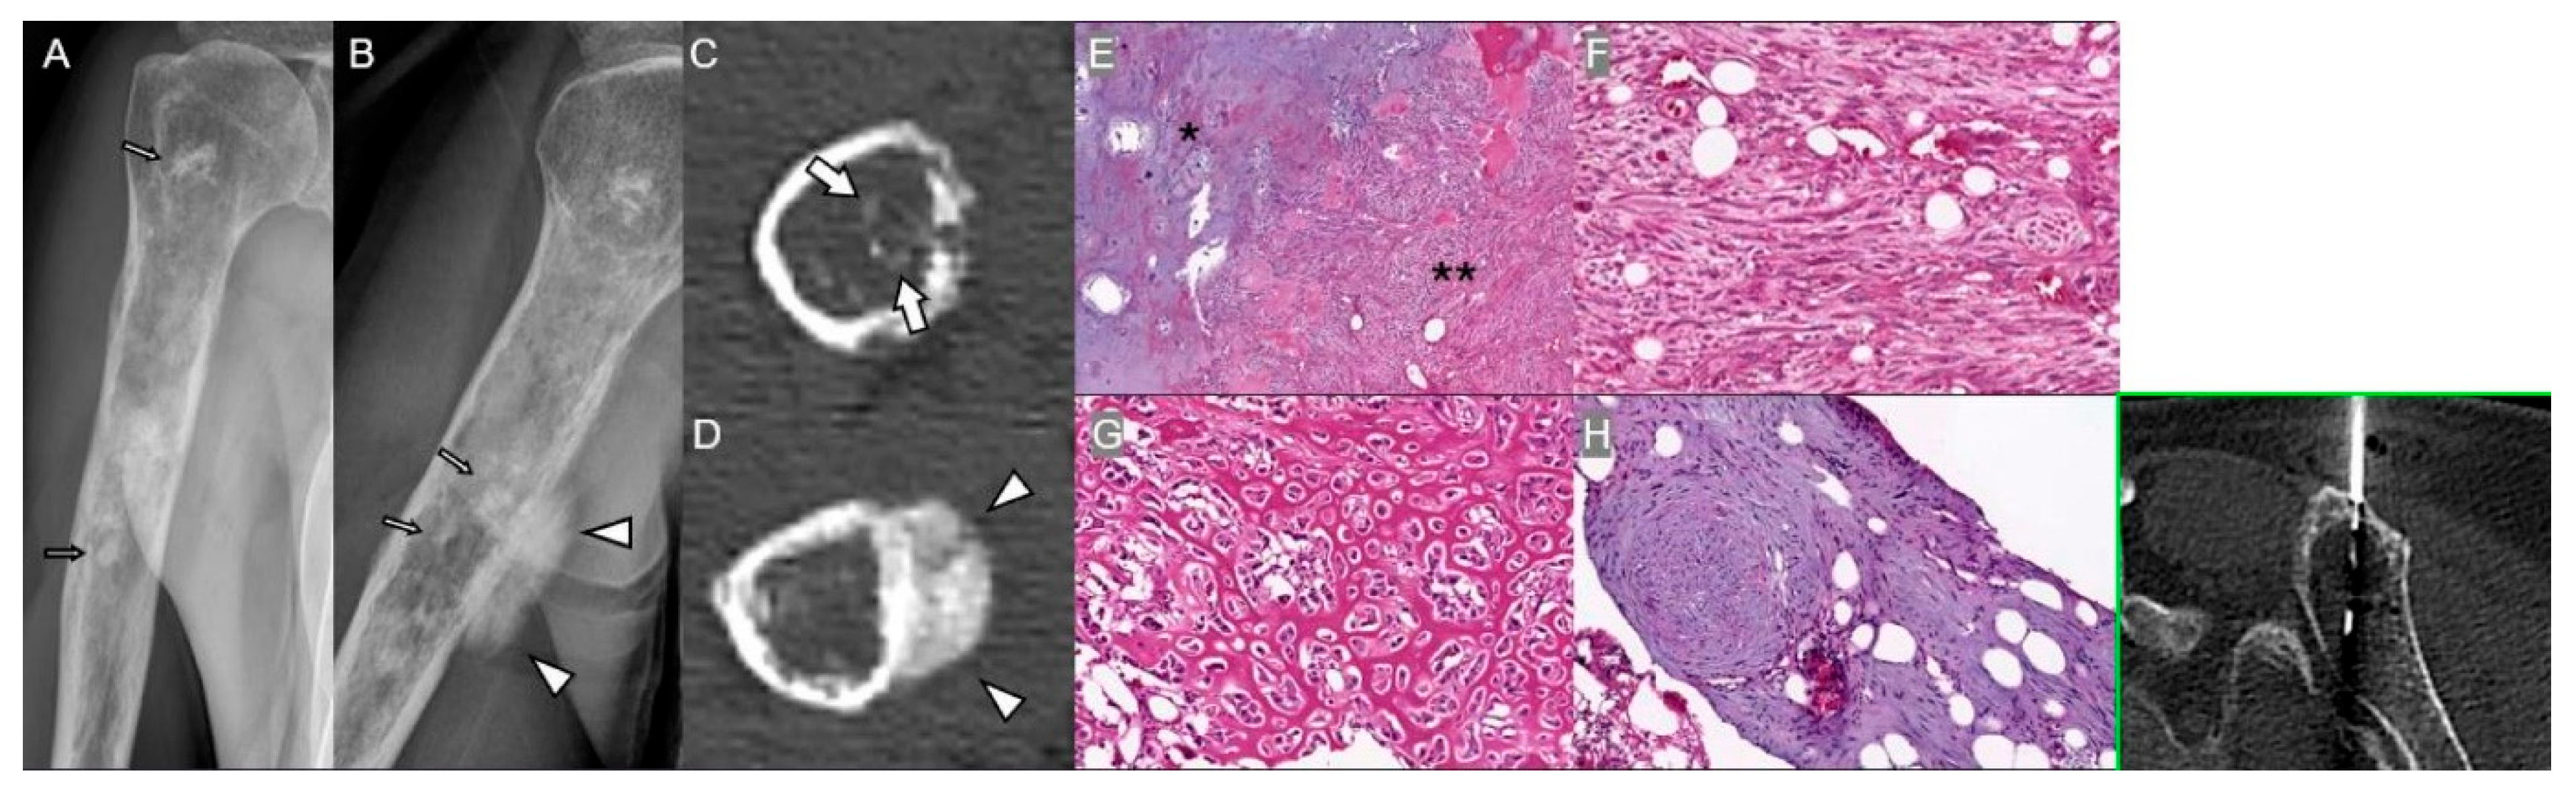

3.1. Chronic Osteomyelitis